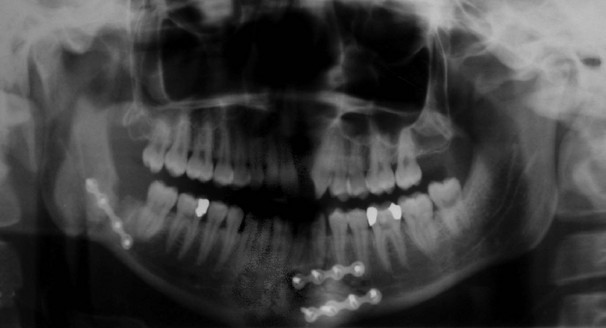

The common sites of mandibular fractures are shown in Figure 16.9. Because of the effects of oblique trauma, a fracture on one side is often accompanied by a fracture on the other side in a different position, e.g. body of mandible on one side and condylar neck on the other. Fracture lines tend to occur through points of weakness, e.g. mental foramina, unerupted third molar teeth or condylar necks. Most undisplaced mandibular fractures need no active intervention but displaced fractures require fixation. This can be achieved by wiring the lower teeth to the upper teeth, by direct wiring of the bones or (more often these days) by internal plate fixation (see Fig. 16.10). Any fracture passing through a tooth socket defines the fracture as ‘compound’ and prophylactic antibiotics should be administered.

Fractures of the middle third of the facial skeleton range from detachment of the palate and dental arch to complete separation of the middle third complex from the skull base. Diagnosis is based on clinical assessment. A simple test is to grasp the upper teeth or jaw between the fingers and attempt to move them independently of the skull. Treatment may involve disimpaction and usually requires sophisticated external fixation to the skull or internal plate fixation afterwards.